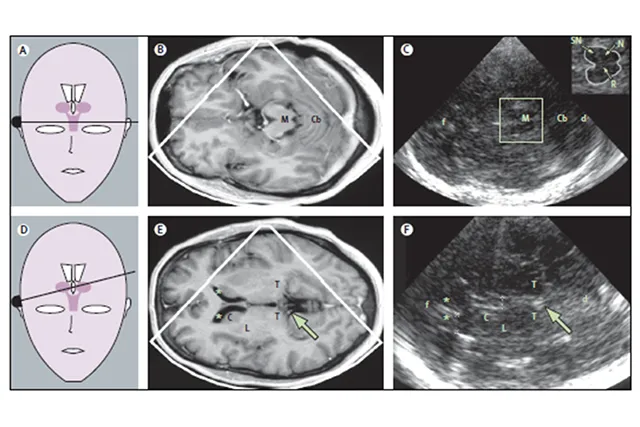

Транскраниальная сонография